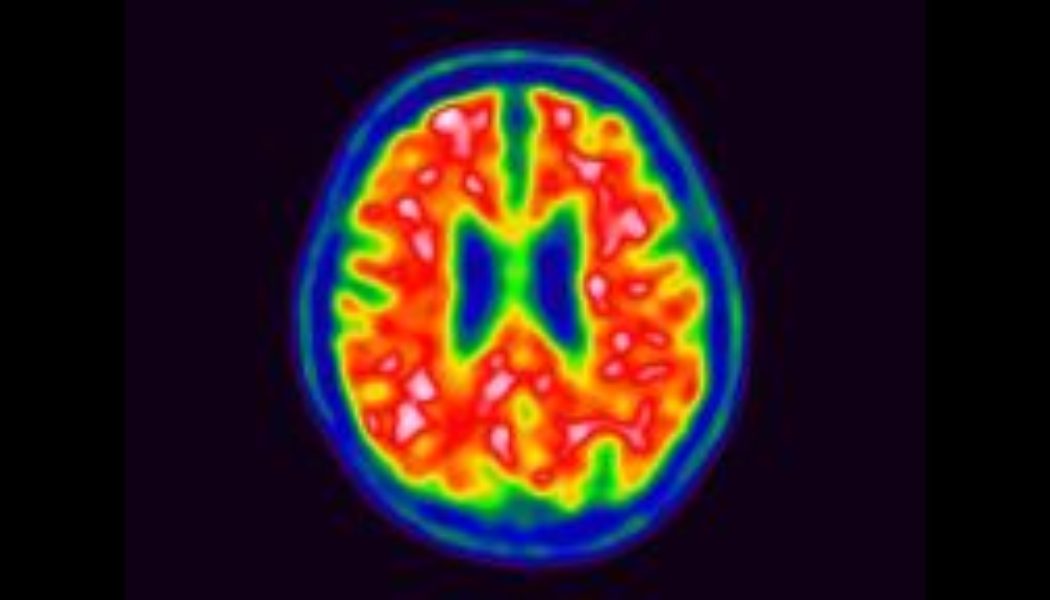

The report offers the first estimates of Alzheimer’s disease prevalence in the US at the county level. Researchers used data from thousands of individuals who participated in the Chicago Health and Aging Project to assess demographic risk factors for Alzheimer’s disease — including age, gender and race — and mapped that against the makeup of US counties.

These demographic estimates suggest that Alzheimer’s rates are highest in Miami-Dade County, Baltimore, and the Bronx — where about 1 in 6 seniors have the disease. Maryland has the highest prevalence at the state level, followed by New York and Mississippi.